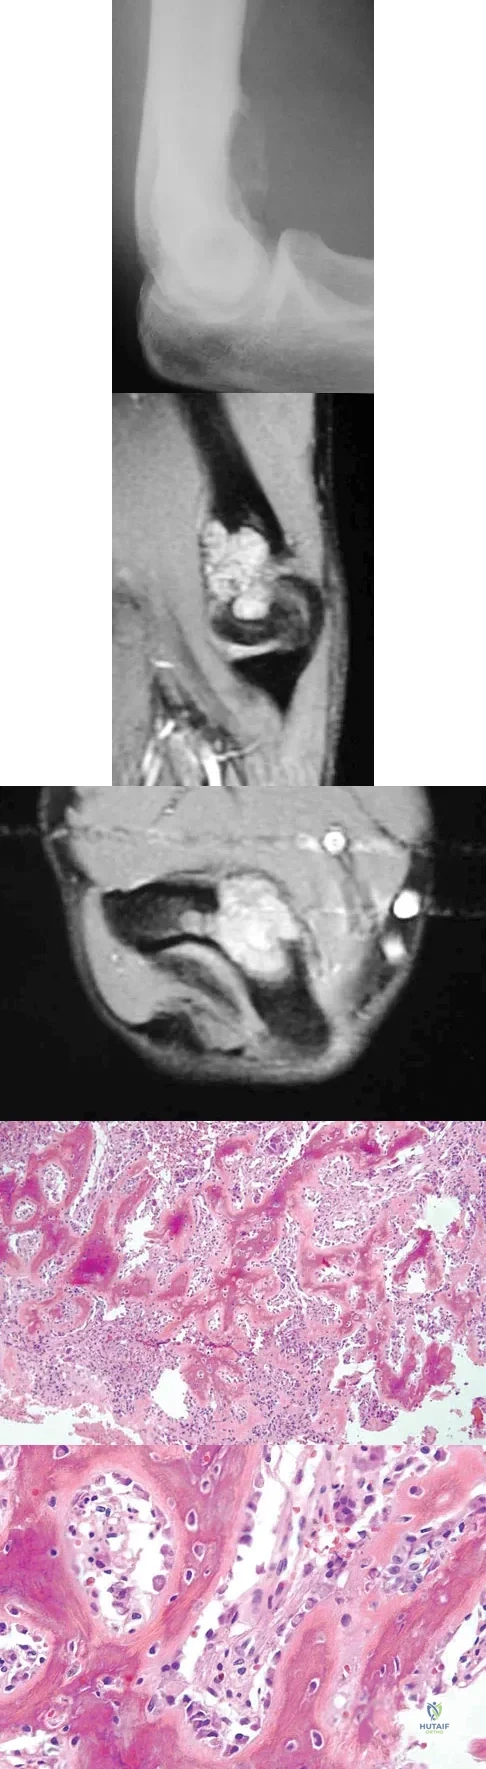

Question 68

A 21-year-old man has mild but persistent aching pain in his left proximal thigh during impact loading activities. He denies pain at rest and has no other symptoms. Figures 34a through 34e show the radiographs and T1-weighted, T2-weighted, and gadolinium MRI scans of the left hip. What is the most likely diagnosis?

Explanation